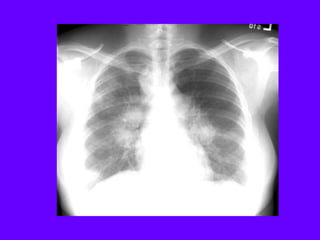

Diffuse Alveolar Pneumonia

The most common causes for diffuse alveolar pneumonia are:

Pneumocystis

Cytomegalovirus